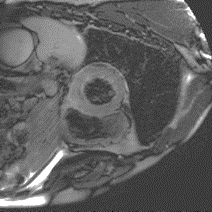

Although supervised deep-learning has achieved promising performance in medical image segmentation, many methods cannot generalize well on unseen data, limiting their real-world applicability. To address this problem, we propose a deep learning-based Bayesian framework, which jointly models image and label statistics, utilizing the domain-irrelevant contour of a medical image for segmentation. Specifically, we first decompose an image into components of contour and basis. Then, we model the expected label as a variable only related to the contour. Finally, we develop a variational Bayesian framework to infer the posterior distributions of these variables, including the contour, the basis, and the label. The framework is implemented with neural networks, thus is referred to as deep Bayesian segmentation. Results on the task of cross-sequence cardiac MRI segmentation show that our method set a new state of the art for model generalizability. Particularly, the BayeSeg model trained with LGE MRI generalized well on T2 images and outperformed other models with great margins, i.e., over 0.47 in terms of average Dice. Our code is available at https://zmiclab.github.io/projects.html.